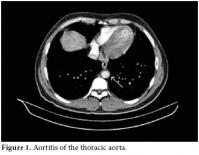

A 28-year-old male patient was admitted to our hospital with complaints of severe abdominal pain and nausea which had started six weeks previously. There were painful, maculopapular lesions that responded well to a topical steroid in both of the palms. The patient had also been suffering from photosensitivity for the last eight months. He had been diagnosed with type 1 diabetes mellitus (DM) and prothrombin 20210a gene mutation during the last 12 years and he had also a history of deep vein thrombosis (DVT) in 2002 and pulmonary thrombo embolism (PTE) in 2006. His mother also had a history of prothrombin 20210a gene mutation and type I DM. He was being treated with a daily dose of glargine insulin and warfarin. His physical examination at the time of admission revealed hypertension (170/100 mmHg), maculopapular lesions on both palms, hepatosplenomegaly, and abdominal tenderness. The laboratory examination was as follows: white blood cells (WBC) counts 15000/mm3, hemoglobin 16.3 gr/dl, platelets 92 000/mm3, blood urea nitrogen (BUN) 20 mg/dl, creatinine 1.46 mg/dl, erythrocyte sedimentation rate (ESR) 40 mm/h, C-reactive protein (CRP) 8.8 mg/dl (0-0.8), and fibrinogen 712 mg/dl (219-403). A urinalysis presented the following results: +++protein, +++blood, no casts, and microprotein in 24 h urine 900 mg/day (0-80). The serologic tests were the followiong: anti-nuclear antibodies 1/320 (homogeneous pattern), anti-double-stranded deoxyribonucleic acid (anti‐dsDNA) 1.7 (0-1.1), rheumatoid factor 22.0 IU/mL (0-15), anti-cardiolipin IgG>300 GPL/mL (0-15), and anti-phospholipid IgG 232 GPL/mL (0-15). A chest X-ray showed minimal pleural effusion and the electrocardiography ECG was normal. There was no thrombus and no vegetation in the transesophageal echocardiography (TEEC). For further evaluation of the thrombocytopenia, bone marrow aspiration and a biopsy were performed, but there were no pathological findings to explain the situation. Also, a skin biopsy from the palms was done to search for the etiology, but this also yielded no clues. Angiography with abdominal computed tomography revealed a thickening of the wall of the thoracic and abdominal aorta and an increased density of the surrounding fat tissues at the level of bifurcation. These were compatible with the diagnosis of vasculitis and retroperitoneal fibrosis (figures 1 and 2).